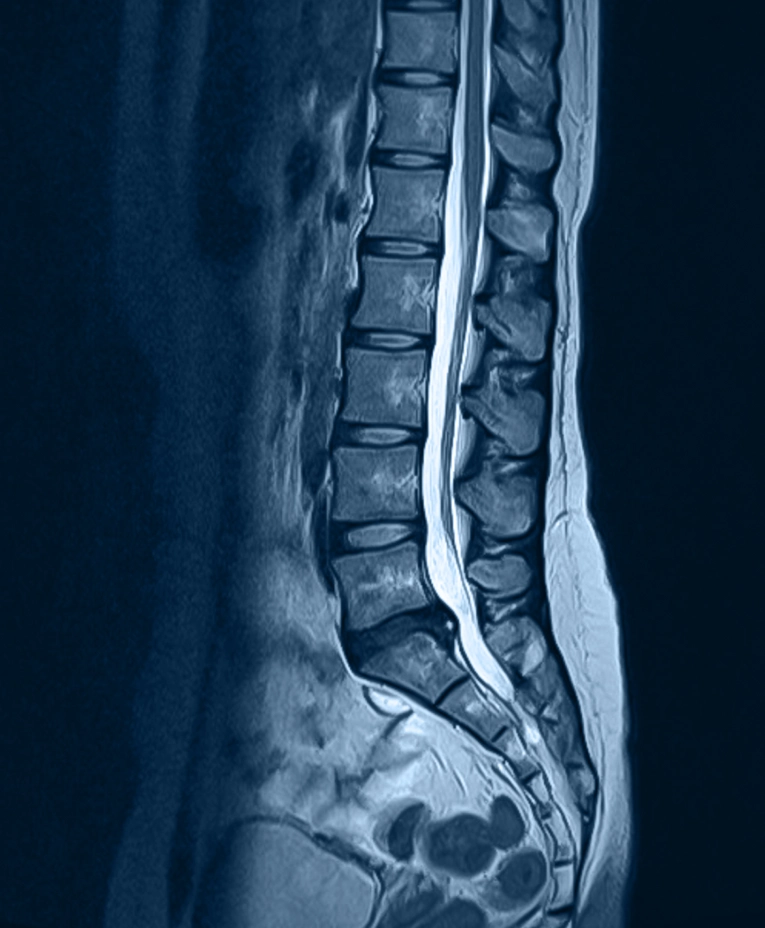

- MRI imaging to detect disc changes

Because tears can be small, they don’t always appear clearly on imaging, making clinical evaluation especially important.

Diagnosis usually starts with a physical exam and a review of your symptoms, activity limits, and pain patterns. Imaging, such as an MRI, may help identify a disc tear or related disc damage, but doctors also compare the scan results with your symptoms because some disc tears do not cause pain.